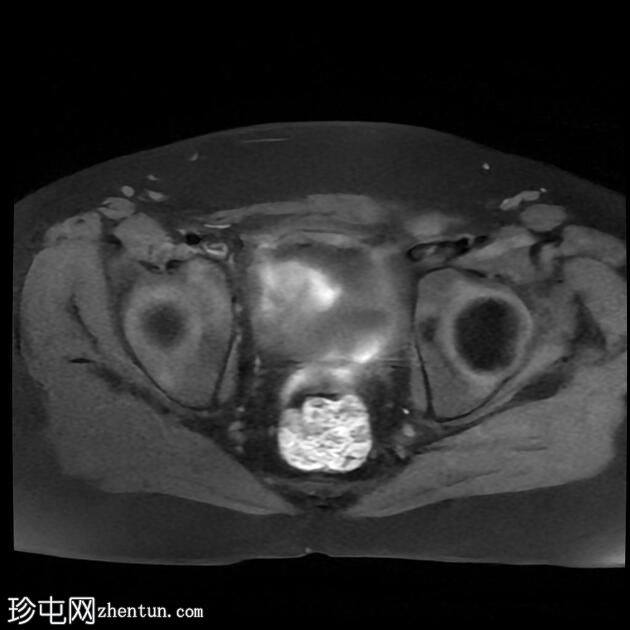

1.jpg

矢状面

T2

MRI序列显示:

女性外生殖器

子宫、宫颈及阴道上2/3缺失

左侧睾丸及腹股沟管内环

右侧睾丸位于腹腔内,靠近腰大肌

双侧卵巢未显影

MRI结果提示雄激素不敏感综合征 (AIS),患者基因构成为男性,但外生殖器为女性(46XY核型)。由于细胞对睾酮等雄激素产生抵抗,雄激素不敏感综合征常伴有双侧隐睾。